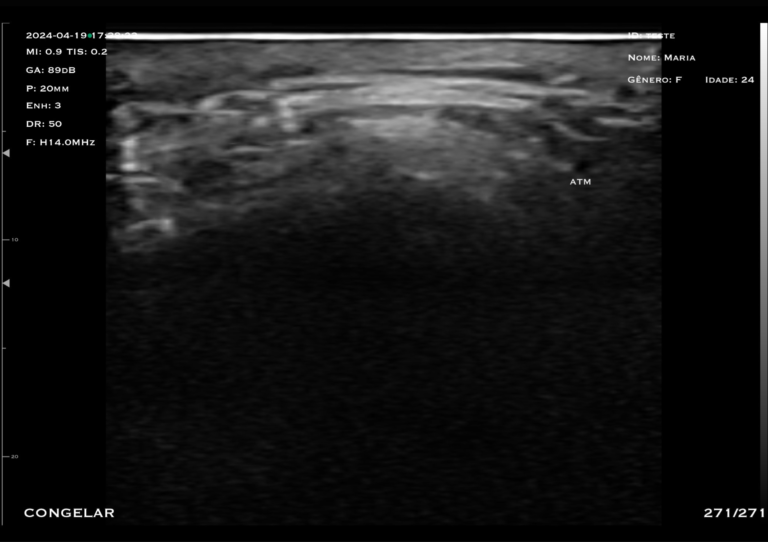

Com tecnologia linear de alta frequência (10 a 14 MHz), o modelo M4D é a escolha ideal para quem busca alta resolução em exames superficiais, com foco em detalhamento e precisão.

O trasdutor linear oferece imagens nítidas e detalhadas, permitindo a visualização precisa de estruturas como pele, tecido subcutâneo, músculos, tendões e articulações.

A alta frequência garante excelente resolução para exames que exigem detalhamento extremo.

Bloqueios de nervos e músculo esquelético, punções superficiais, infiltrações, TAP Block, mensuração de tecido adiposo e entrada de acesso central.